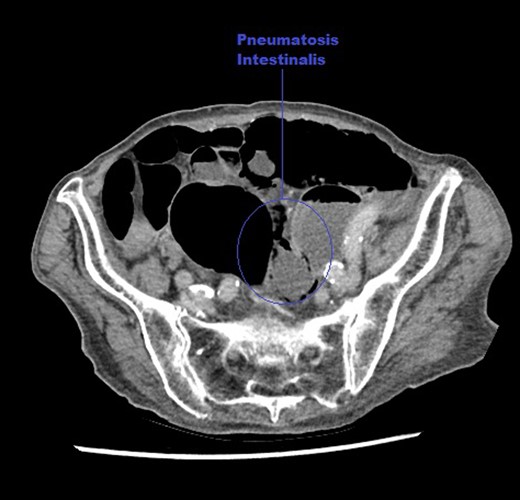

An axial CT image of the abdomen taken at initial presentation, demonstrating PI marked on the image.